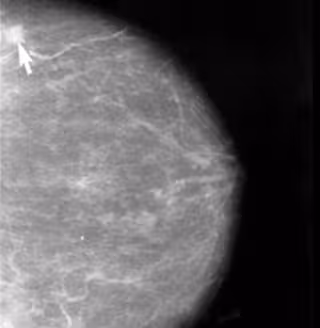

Marcar pequeños tumores no palpables de mama con semillas de yodo 125 permite una cirugía más conservadora, más eficaz y de menor duración, según ha asegurado la responsable de la implantación de esta técnica en MD Anderson Madrid, María Eugenia Rioja.

En cuanto a la implantación de la semilla de yodo en el tumor de mama para una posterior cirugía, Rioja ha explicado que se pincha la mama y se controla normalmente con una ecografía dónde se quiere llevar la aguja y, una vez allí, se libera la semilla. Un mecanismo que puede realizarse hasta tres y cuatro días antes de la intervención quirúrgica.

Una vez en quirófano, el cirujano utiliza los rayos X para localizar la semilla de yodo 125 y un detector externo de radiactividad para "sentir" la actividad de la lesión y proceder a su extirpación. "Son cantidades de irradiación despreciables, muy bajitas. Utilizamos siempre una actividad tan baja como es posible pero que nos permita detectar la lesión", ha apostillado la experta.

Aunque se utiliza en tumores de mama principalmente, es posible utilizar esta técnica también en lesiones benignas de mama como, por ejemplo, las microcalcificaciones. Asimismo, últimamente se está utilizando esta técnica en lesiones no palpables por el cirujano y que se ubican en zonas como el abdomen, los músculos o el pulmón, con muy buenos resultados.